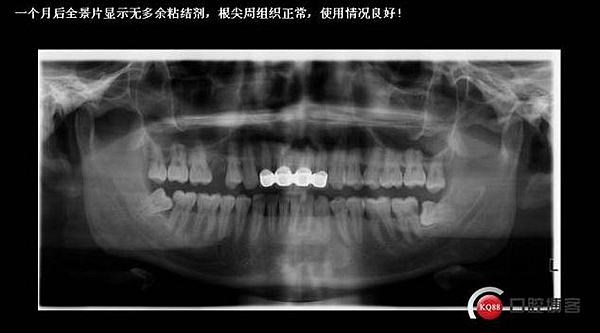

口內(nèi)檢查:很輕易就取下牙冠,均為殘冠殘根且繼發(fā)齲,#21尤為嚴(yán)重,已到齦下,牙周探診1.5mm,X線檢查:根尖陰影,欠充。

診斷:#11#21殘根,繼發(fā)齲,輕度牙周炎。